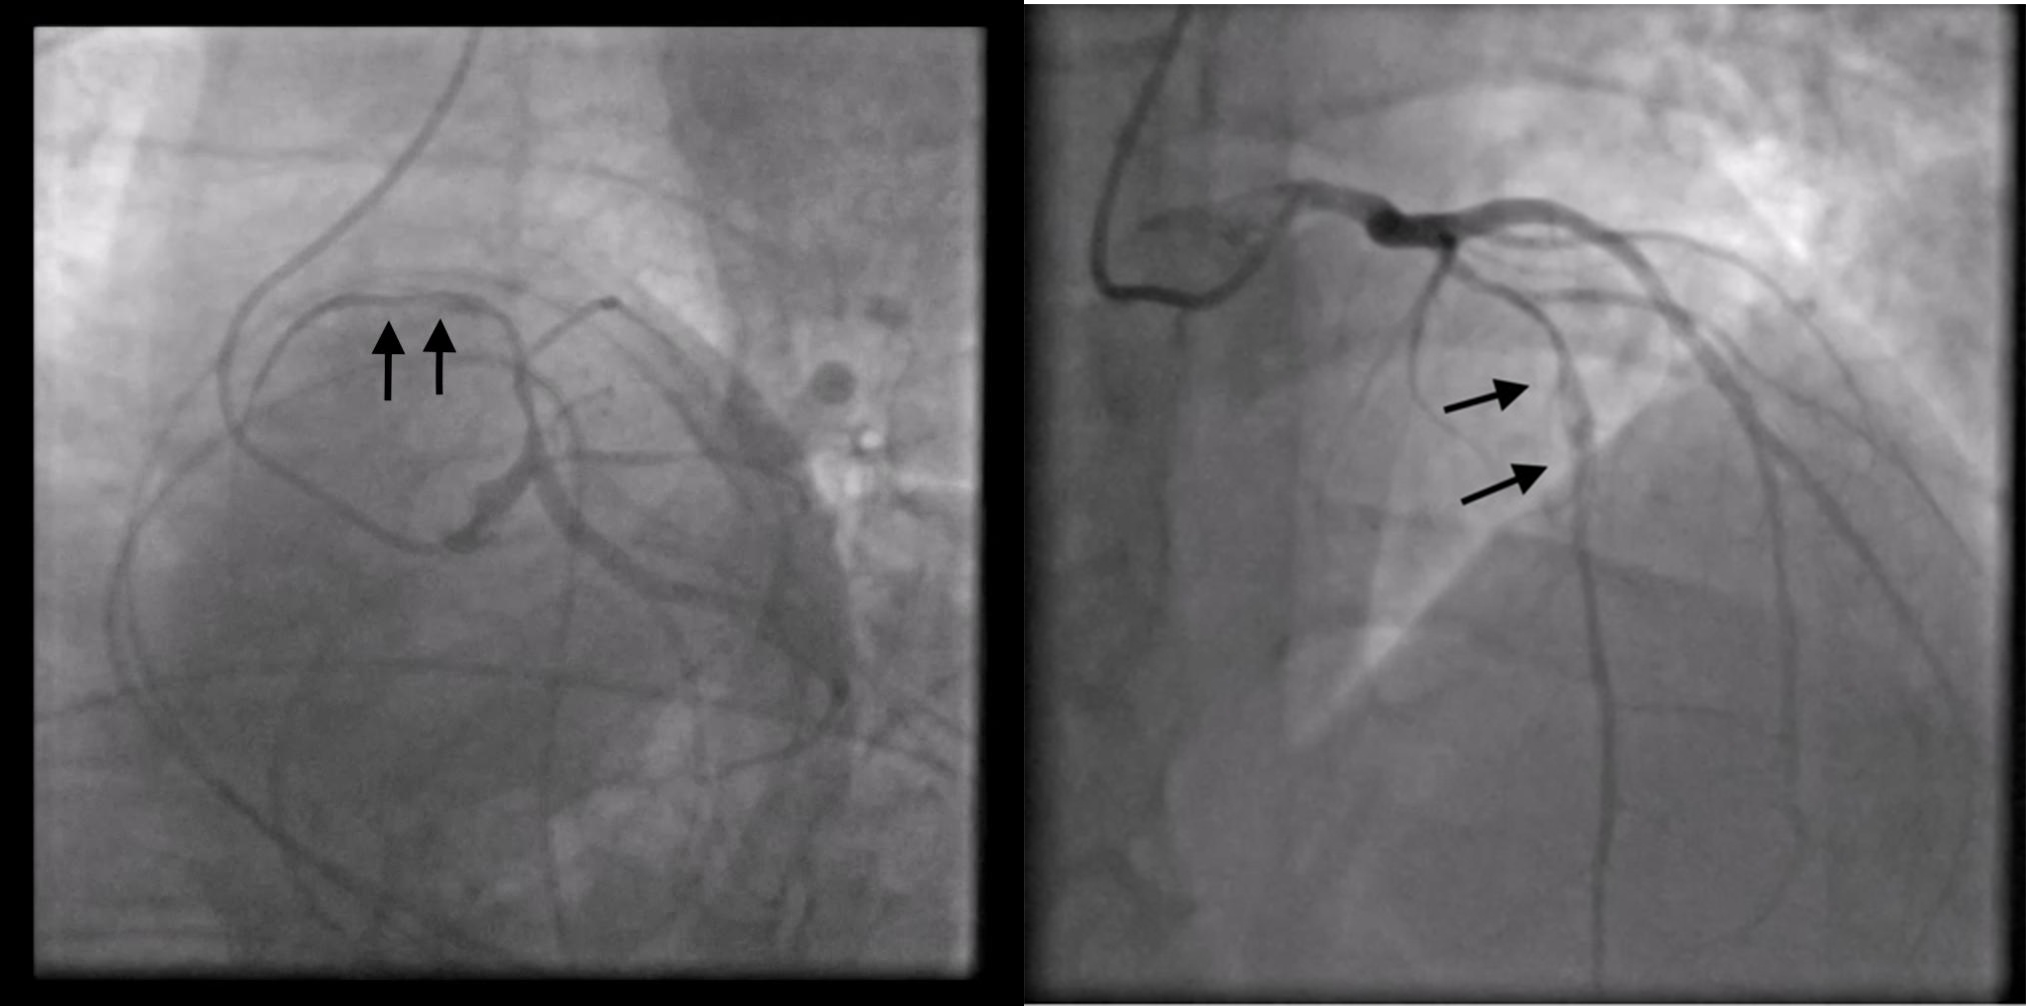

The new hs-troponin test results, showing a new peak of myocardionecrosis markers of 289 ng/L, came when the patient had already been transferred to the CICU, where, finally, an emergency coronary angiography (CAG) was performed. Surprisingly enough, the CAG showed no stenosis; instead, it revealed a spontaneous dissection evident in the middle tract of the LAD coronary artery; this was classified as a type 2 dissection of the LAD coronary artery according to the European Society of Cardiology (ESC) classification (Fig. 6). The angiographic images show a plausible proximal extension of the dissection, where the vessel appears diffusely reduced in caliber; however, the same findings could also be indicative of diffuse atherosclerotic disease in the proximal LAD artery. In the acute setting, given the high suspicion of proximal extension, it was not deemed appropriate to use intracoronary imaging techniques such as intravascular ultrasound (IVUS) or optical coherence tomography (OCT) because of the associated risks of catheter-induced dissection propagation, potentially aggravating the patient’s condition and endangering her life.

Fig. 6.

Fig. 6.Coronary angiography shows no stenosis; instead, it reveals a spontaneous type 2 dissection of left anterior descending (LAD) coronary artery.